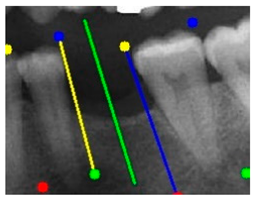

| Comparison with dentist’s ground truth (black line) and our framework (green line) | ||||||

| Validation Image 1–6 | ![]() | ![]() | ![]() | ![]() | ![]() | ![]() |

| MSE | 3.59 | 1.29 | 0.41 | 0.80 | ||